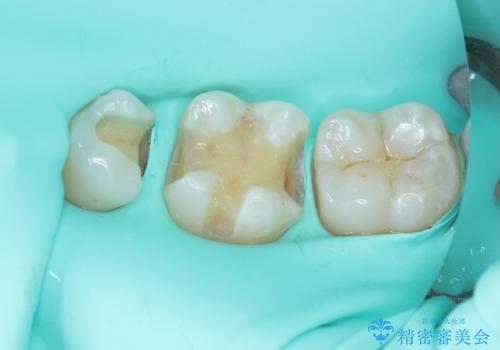

まず麻酔をして銀歯を外し、むし歯を除去し、形を整えて型取りします。

そして次の来院時、セラミックインレーを装着し、噛み合わせなどの調整を行います。

インレーを装着するときは、唾液や血液による接着力の低下を避けるためにラバーダム防湿を行いました。